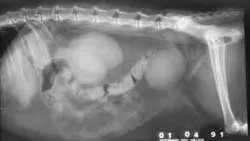

Abdominal radiographs will show only an enlarged kidney or kidneys (Figure 2A), but excretory urography will show renal pelvis dilatation (Figure 2B). Ultrasonography will also show hydronephrosis, renal parenchymal disarray, and necrotic debris in the renal collecting system (Figure 3).

Abdominal radiographs of a cat with bilateral pyonephrosis; a cystotomy performed 6 months previously had caused bilateral ureteral obstruction at the urethral junction (A and B). Pyelography was done by pyelocentesis, and bilateral hydronephrosis is shown.